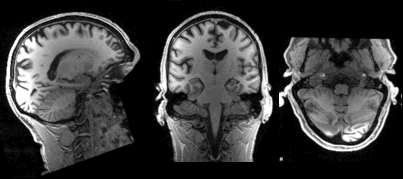

An MRI Scan from the Open Database

The workshop touched upon several functions we could use to manipulate MRI images such as creating a brainless head and headless brain, identify different parts of the brain, looking at MRI images from different points of view, and slicing the brain along different axes. We learned about how to apply these functions to multiple brain images instead of only one.

So how is it different from MRI? The MRI generates 3D scans of the brain. They are like static 3D images. fMRI adds a time dimension to these images as it is detecting changes in the blood flow. This results in the creation of activation maps that show which parts of the brain are activated at what time.

The workshop introduced us to Neuroimaging Informatics Technology Initiative or NIfTI files. NIfTI is one of the most ubiquitous file formats for storing neuroimaging data. We learned how to pre-process fMRI data, how to open NIfTI files into Python, and how the data is stored in these files. These are essential steps before we can carry out any analysis of data or manipulation of images.

Again, we learned how manipulation can be done on DMRI images. It used the same libraries as was the case with fMRI analysis. We learned about querying the data, dimension reductions, taking 2D images out of 3D scans, understanding the signal intensity of the voxel at coordinates. Voxels or volume pixels were my favorite part. Voxels are the smallest distinguishable box-shaped part of a three-dimensional image that is generated in an MRI scan. We learned about flipping color scales so that black portions appear white and vice versa.